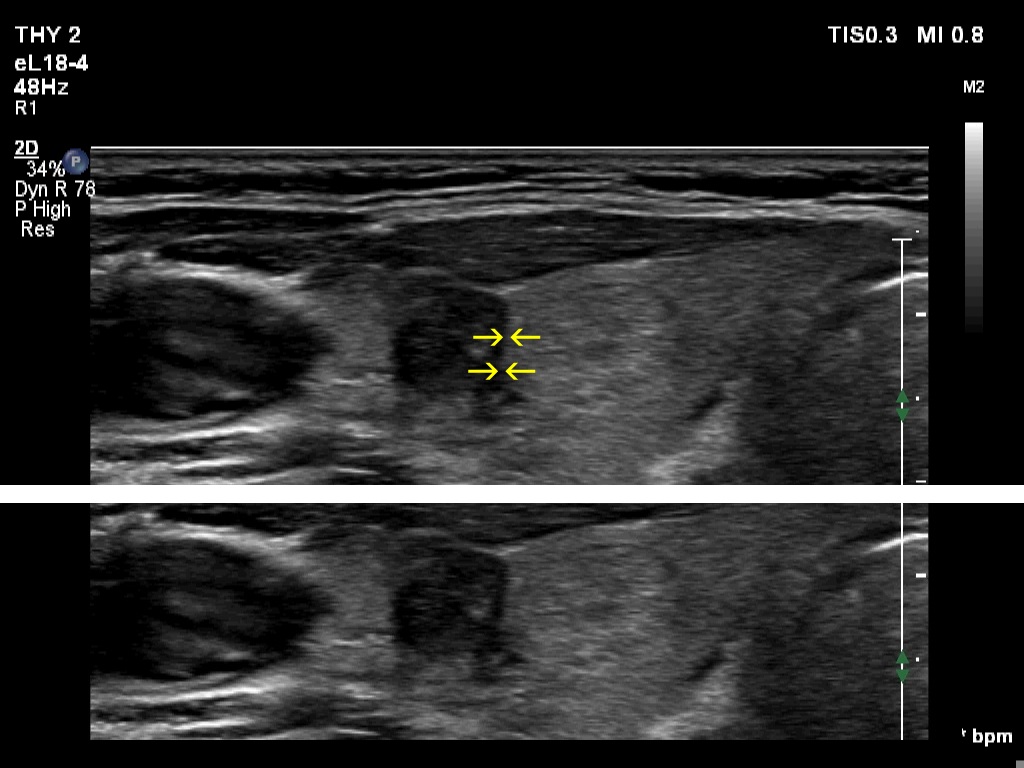

The shape of the nodule - case 2255 (ultrasonographic picture 6c)

Right lobe, transverse scan, enlargement. The yellow arrows point to the borders between the lateral hypoechoic and the medial echonormal nodule. We have to realize that the latter nodule hinders the spread of the hypoechoic lesion into medial direction. It means that the width of the nodule is deceptively lower and the taller-than-wide shape is simply the consequence of the presence of and impression caused by the neighboring other nodule.